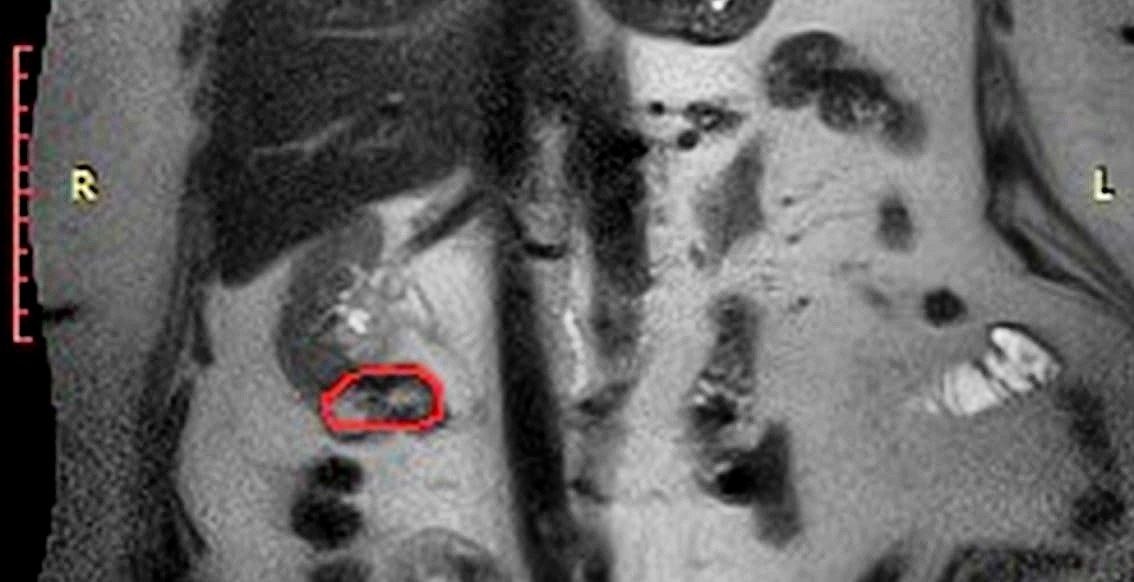

Ранее женщине уже удалили левую почку, а также сделали частичную резекцию правой почки. Однако на плановом контрольном обследовании врачи выявили рецидив опухоли в оставшейся почке.

Специалисты онкологического отделения приняли решение о проведении органосохраняющей операции. Хирурги удалили опухоль, остановив кровообращение в почечных сосудах на семь минут, что позволило минимизировать риски осложнений.